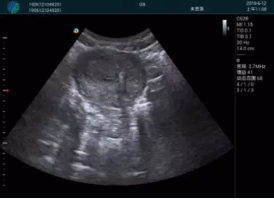

M20查看:囊內回聲均勻,邊界清晰,囊壁光滑

M20引導抽吸術(shù)后囊腫消失,原區域空腔形成,脂肪層與腺體層架構發(fā)生改變